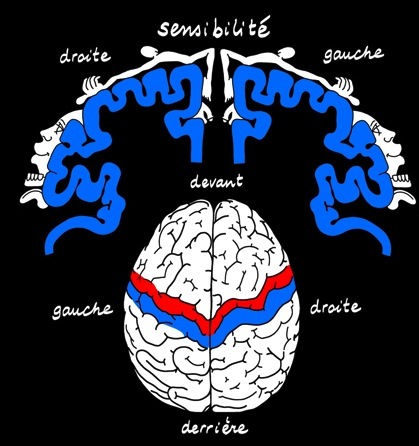

Le cerveau reçoit et transmet des informations récoltées à l'extérieur (environnement) et à l'intérieur par nos sens : ces sensations prennent la voie ascendante des nerfs sensitifs.

Le thalamus (noyau gris) est un relais des voies nerveuses ascendantes.

C'est dans l'aire somatosensorielle (ou somesthésique) que la perception est enfin réalisée. Le message repart dans plusieurs directions.

L'aire du langage envoie un influx à l'aire motrice qui envoie ses ordres à la langue, au larynx ( Aïe ! )